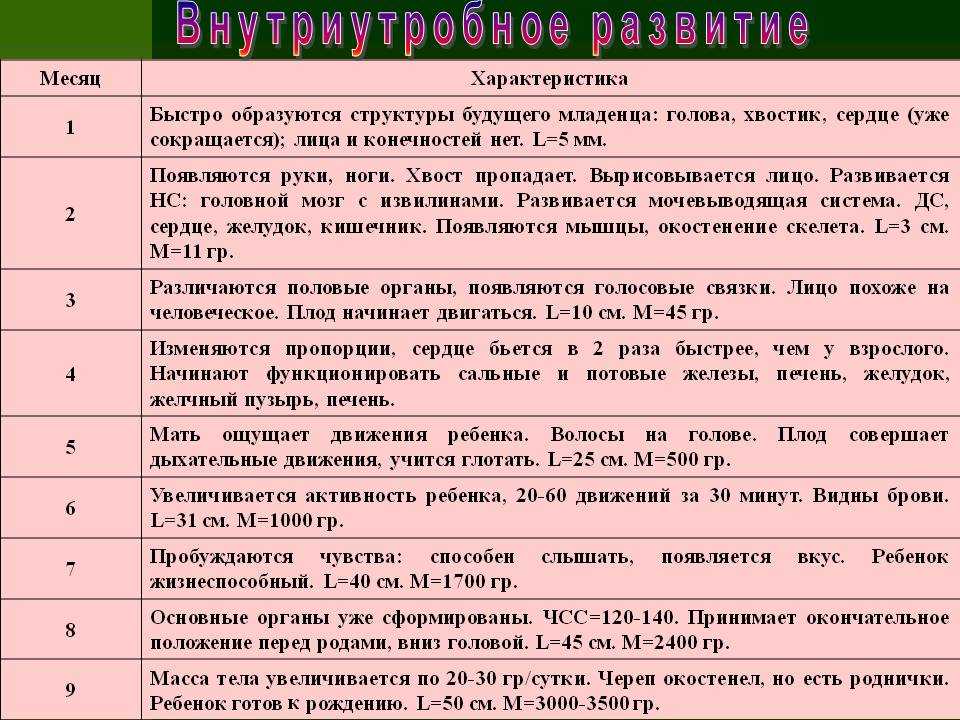

16 недель. Ребенок весит примерно 150 граммов, его рост достигает 16-18 сантиметров. На головке появляются волосы, на лице — реснички и брови. Малыш открывает ротик, глотает, сосет, улыбается. В этот период начинает полноценно функционировать плацента, которая связывает его с мамой.

20 недель. Рост малыша достигает 30 сантиметров, у него появляются ноготки на пальцах рук и ног. Теперь мама чувствует его движения, так как время от времени он начинает заниматься физкультурой: отталкивается от одной стенки матки и доплывает до другой. Кроме того, ребенок может отреагировать на резкий звук или волнение матери прыжком, который воспринимается как активное шевеление. Если же малыш начинает икать, женщина ощущает слабые ритмичные толчки, идущие изнутри. В 20 недель врачи выслушивают сердцебиение малыша с помощью стетоскопа.

24 недели. Малыш уже может рассердиться. Это доказывает фотография ребенка в этом возрасте. На ней видны его сердитый взгляд, напряжение мышц вокруг глаз, сморщенные губки, видно, что он плачет, выражая свое недовольство. Кстати, чтобы отдохнуть ночью, малыш ложится спать и… видит сны. Ребенок весит около 500 граммов это немного, но он только начал набирать вес. Его кожа красная и морщинистая. Так как она еще очень нежна, малыш защищается от воздействия околоплодных вод специальной смазкой. К 24-й неделе беременности начинают функционировать жировые и потовые железы, созревают легкие ребенка. В них образуется пленка, которая не дает им склеиваться при дыхании. Если ребенок родится в это время и будет обеспечен необходимой заботой, он сможет выжить.

8-й месяц: 29-32 недели

С каждым днем ребенок все больше и больше подготавливается к предстоящей жизни вне организма мамы и родам. Он уже весит около 1,5-1,6 килограмма и достигает в длину 40 сантиметров. Сейчас он занимает почти все место в матке, поэтому движения его очень рациональны. Он уже не «плавает», а совершает более точные движения ручками и ножками.

10-й месяц: 37-40 недель

Итак, на 10-м месяце все системы ребенка готовы к рождению. Работает пищеварительный тракт: ворсинки кишечника продвигают первородный кал вниз к толстому кишечнику, работает желудок, поджелудочная железа вырабатывает пепсин, необходимый в пищеварении.

Однако пищеварительная система ребенка в утробе абсолютно стерильна, все нужные бактерии, которые помогают переваривать и усваивать пищу появятся только в период лактации из грудного молока матери.

Заканчивает развитие половая система – у девочек большие половые губы закрывают маленькие, у мальчиков яички в большинстве случаев опускаются в мошонку.

Надпочечники настолько увеличиваются в размерах, что становятся больше почек, так как на их долю приходится выработка гормонов стресса во время родов – адреналина и норадреналина.

Кости черепа и швы остаются мягкими и податливыми. 2 родничка – теменной и затылочный помогают черепу принять удобную форму, чтобы пройти по родовым каналам матери без травм.

4-й месяц: 13-16 недель

В четвертом месяце ребенок очень быстро растет – вырастая на 3-8 сантиметра в длину (к концу четвертого месяца – 12-17 см) и увеличивается в весе почти в десять раз с 25 грамм в третьем месяце до 200 грамм.

Самое важное достижение этого месяца – это движение!

Плод начинает рефлекторно двигаться, он совершает не только простые движения – двигает головой, руками, ногами, но и сложные – находит кулачком рот, начинает сосать палец, находит руками пуповину. Женщины, которые рожают не в первый раз, могут почувствовать его движения, они очень слабые и едва ощутимые, но их можно уловить.

Начинает работать вся пищеварительная система.

У ребенка появляются первые вкусовые ощущения, он реагирует на те вещества, которые растворены в амниотической жидкости – на сладкое – активным глотанием, на горькое и кислое – самым минимальным. Именно это глотание дает тренировку всей пищеварительной системе. Активно работает выделительная система, моча выводится с помощью плаценты в кровь матери.

Ребенок переходит с гормонов мамы, на свои собственные и гормоны плаценты.

И с этого месяца может даже делиться гормонами с мамой. Гормоны играют потрясающе важную роль, именно за счет них ребенок растет и развивается, чем больше и лучше плод снабжается гормонами, тем лучше и быстрее он растет.

В этом месяце кровь ребенка содержит все клетки взрослого человека и уже можно определить его группу крови и ее резус-фактор.

К 16 неделе формируются наружные половые органы, и вы можете узнать пол своего будущего ребеночка, конечно если он повернется как нужно во время УЗИ.